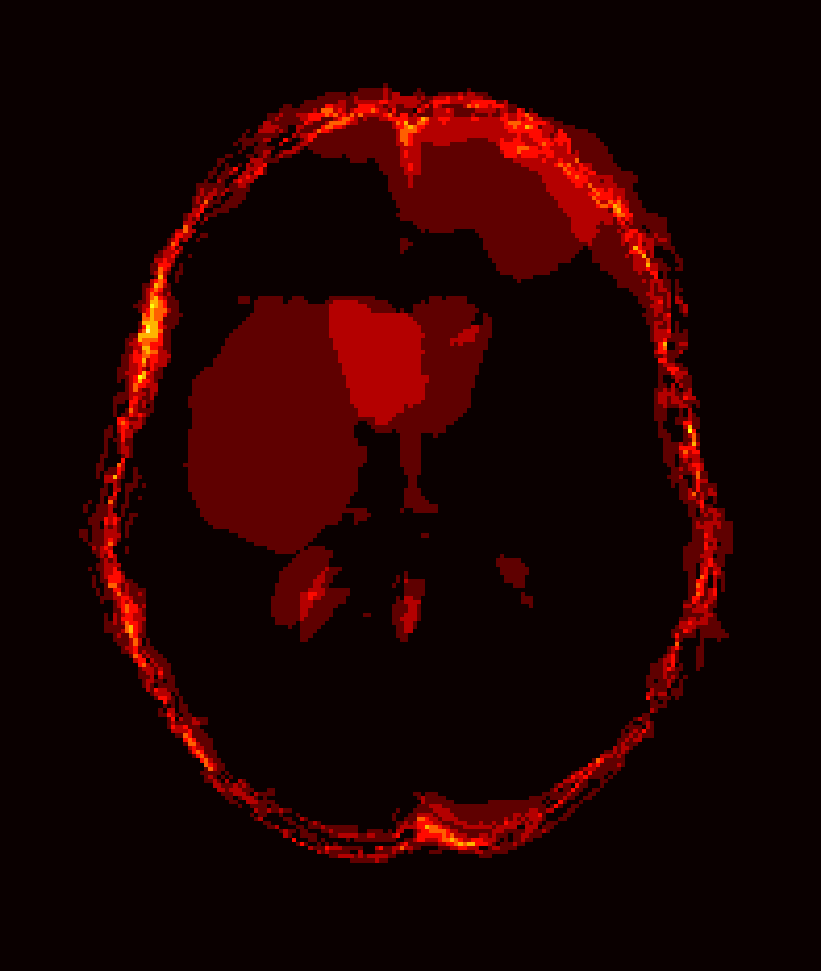

Fig. 1 shows example images from each dataset to illustrate image variability. IBSR and LPBA40 contain images from normal subjects and include large portions of the neck; BRATS has very low out-of-plane resolution; and the TBI dataset contains large pathologies and abnormal skulls.

Refer to caption

Figure 1: Illustration of image appearance variability on a selection of images from each (evaluation) database. From top to bottom: IBSR, LPBA40, BRATS and TBI.